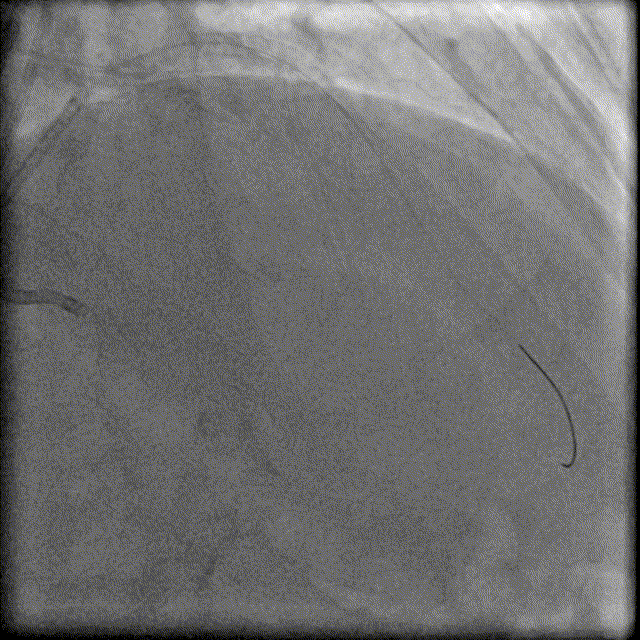

6F EBU3.5指引导管置于LM, 6F AL0.75 SH指引导管置于RCA,Runthrough 指引导丝至LAD远端, 2.0×15mm Sprinter球囊、2.5×6mm Wolverine切割球囊以10atm×15秒扩张LAD病变。

于LAD近段植入4.0×18mm Resolute Integrity支架,与LAD原支架衔接2mm,以10atm×15秒释放;4.0×15mm NC Sprinter球囊以12-16atm×15秒后扩。重复造影见残余狭窄<10%,无夹层和血栓,前向血流TIMI-3级。